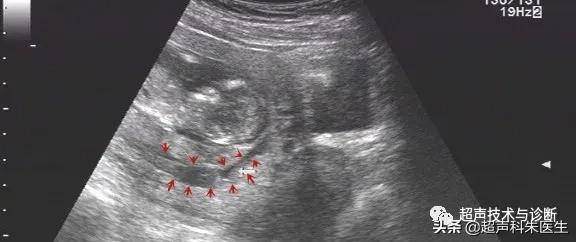

出现绒毛膜下血肿的孕妇,仅有20%会出现阴道不规则流血或下腹部疼痛的症状,而其余大多数绒毛膜下血肿是在超声检查中发现的,其超声表现为:子宫壁和胎膜(或孕囊)之间的无回声区,多位于胎盘下缘至宫颈内口间,以弧形或新月形多见,若血肿较多或血肿形成时间较长时,内可见点、絮状弱回声及条带状强回声,彩色多普勒超声检查:血肿内无血流信号。

接下来我们来看看具体病例: